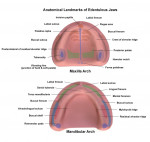

"Capturing borders and landmarks when making final impressions, as well as knowing where to position the teeth in the face and occlusal schemes, are critical concepts to the success of a removable restoration and carry through whether analog or digital techniques are being utilized," says Dean E. Kois, DMD, MSD, an Instructor at the Kois Center and a prosthodontist with a private practice limited to restorative, esthetic, and implant dentistry in Seattle, Washington.

For technicians, understanding basic soft tissue anatomy is the foundation for success with complete dentures; if the necessary anatomy or biology of the denture space cannot be read easily in the negative impression, then it must be taken again until it is correct and all necessary soft tissue anatomy is visible.4 Anatomical landmarks such as the retromolar pads, external oblique, mentalis muscle, frenum attachments, mylohyoid ridge, tuberosities, hamular notches, incisive papilla, labial sulcus, and buccal vestibule are critical and must be captured in the positive (and easily read in the negative) aspect of any edentulous impression.4